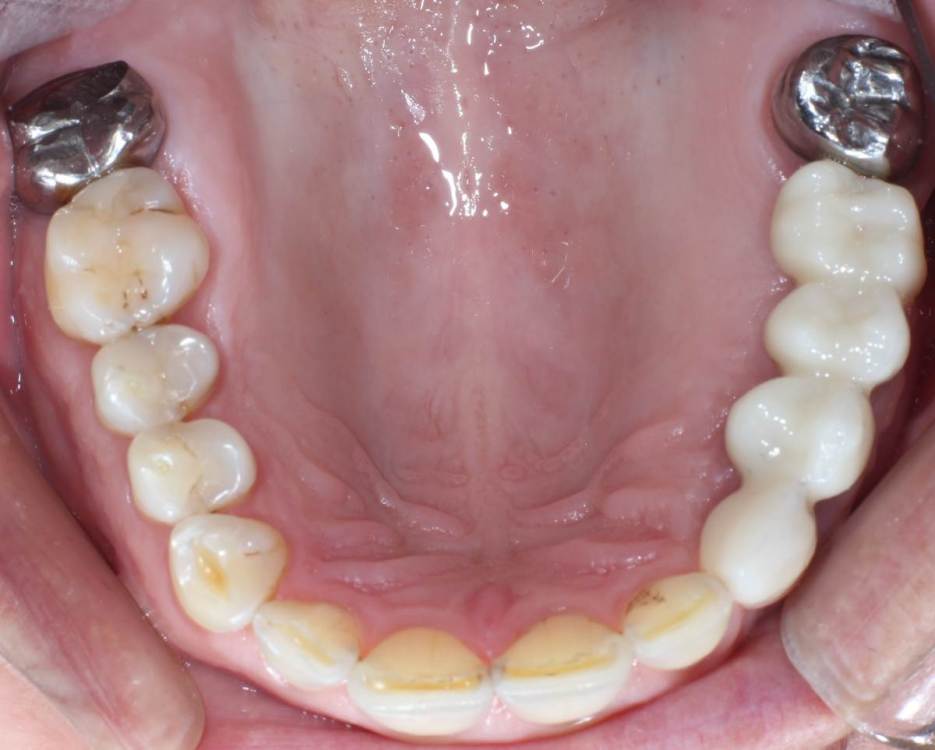

kuziy12 Опубликовано 2 ноября, 2020 Поделиться Опубликовано 2 ноября, 2020 Имплантация с синус лифтингом. Беда с позицией 2.3. Коронки на cad\cam, наносил розовую керамику и красил все сам. Сваливать не на кого) До: После имплантации: Формики: Десна: Постоянная конструкция: Улыбка: 3 Ссылка на комментарий

kuziy12 Опубликовано 9 октября, 2021 Автор Поделиться Опубликовано 9 октября, 2021 Дабы не плодить темы, выложу тут. Докрутил пациента полностью)) Ортопедия тоже моя. От переустановки импланта в области клыка отказалась. Ссылка на комментарий